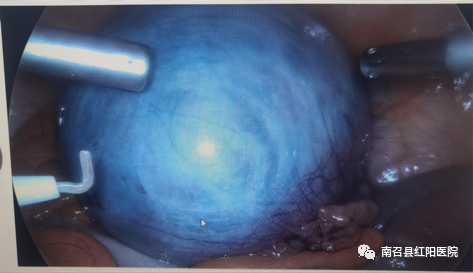

患者王女士,今年67岁,发现附件区囊肿20余年,因无不适未给予定期检查,3个月前自觉下腹部疼痛就诊于我院,彩超提示:右侧附件区囊肿,磁共振结果显示:12x11x225px类圆形包块,考虑浆液性囊腺瘤可能。患者心理负担较重,曾到外院就诊行穿刺术失败,经反复与家属商量并咨询郑州三甲医院医生,最终决定到我院手术治疗,患者经多方打听后表示:“我就是听说你们医院腹腔镜手术技术高超,所以来做微创的。”周顺平主任妇产科团队及手术室团队为患者行全麻腹腔镜下右侧附件切除术,手术非常顺利,历时30分钟,术中几乎无出血。术后患者恢复良好,术后3天即康复出院。